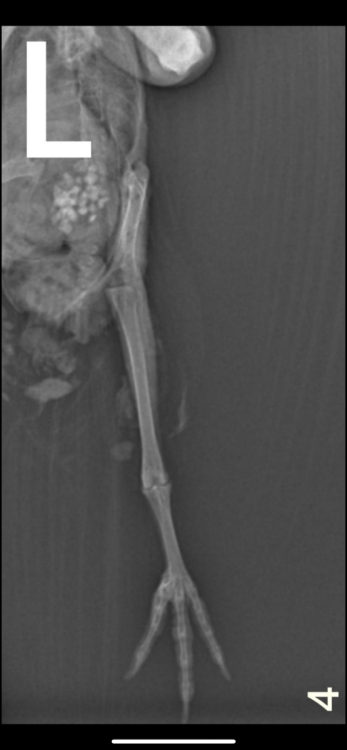

Здравствуйте, неделю назад возле автомобиля обнаружила голубя , лежал на левом боку и не мог встать. Я подумала что сбила машина, взяла его к себе. Съездили к орнитологу , он пощупал лапки , сказал возможно это связано с нервной системой , либо повреждена левая лапа. Голубь, взлетает без проблем. Но не упирается на лапы , теряет координацию и падает + постоянно вся попа в 💩. Кушает хорошо и пьет водичку самостоятельно. Сегодня смотрю , упирается на правую лапу , а левую вытягивает прямо назад.

На всякий случай купила витамины, добавляю по капельки в водичку. Голову не запрокидывает.  Фото рентгена прилагаю. Кто сталкивался с подобным ? Что может быть ?

Возможно есть повреждение бедренной кости- выбита или перелом головки.